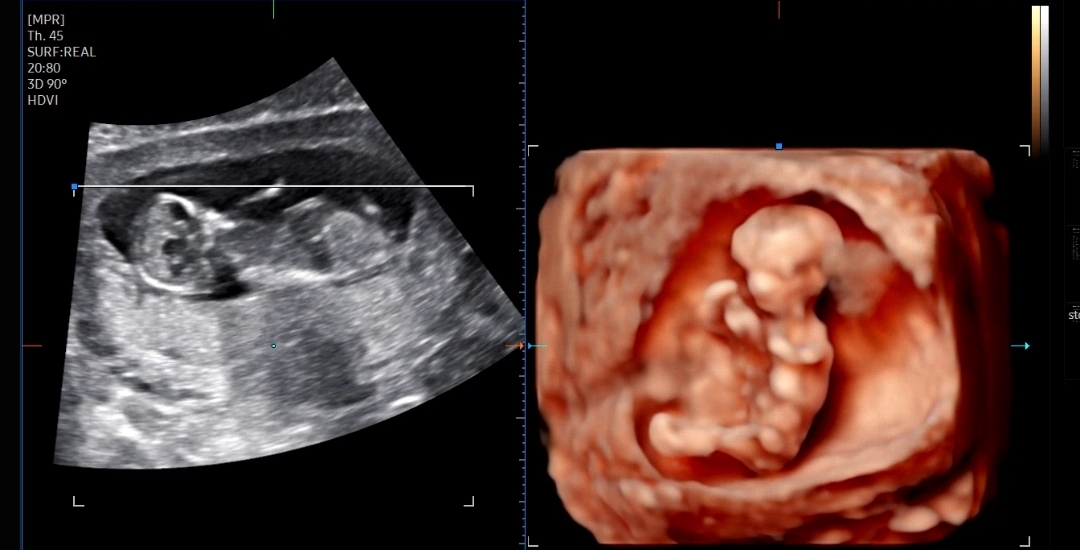

임신 12주 2일 1차 기형아 검사

기형아 검사는 NT(목투명대)를 보는 초음파와 피검사로 시행했고

먼저 예약된 시간된 시간에 맞춰 NT초음파를 보는 초음파실로 갔다

우선 아기크기와 심장소리를 확인했는데 아기크기도 6.26cm, 심장소리도 171bpm으로 잘 뛰고 있었다

처음으로 그나마 사람같이(?) 보이던 입체 초음파 ㅋㅋ

그동안 입체 초음파는 거의 사람형태가 아니어서 굳이 안 보여주셔도 되는데 싶었는데

이번에 처음으로 그나마 사람의 형태 비스무리하게 보였다

마지막으로 확인한 콧대길이, 소뇌?길이, 목투명대 길이를 쟀다

처음에 계속 뒤돌아 있어서 기침하고 했는데 약 10분간 애쓰다가 겨우 보여준 콧대

코뼈길이는 0.26cm, 목투명대는 1.31mm 로 둘다 정상범위!

만약에 코뼈가 낮거나 목투명대가 3mm이상이면 다운증후군 위험이 있다고 했다